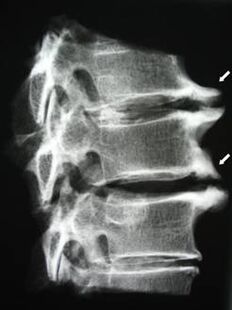

V počiatočných štádiách sa osteochondróza zisťuje pomocou MRI. Neskôr môže byť patológia diagnostikovaná pomocou rádiografie. Na röntgenových snímkach krčnej chrbtice sa prejavuje zmenšenie vzdialenosti medzi stavcami, patologické zmeny fazetových kĺbov a osteofytóza.